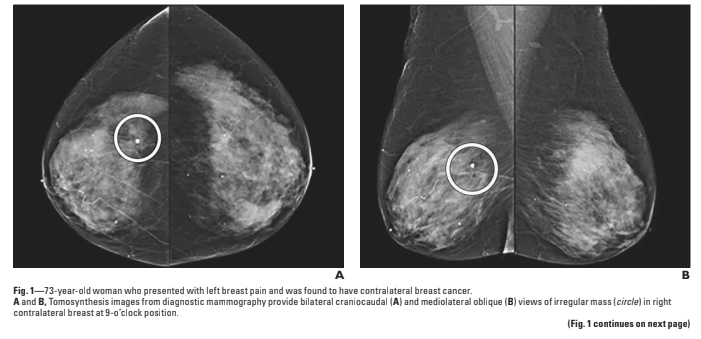

4 patients were described with breast cancer.

What did they find, and was it associated with breast pain?